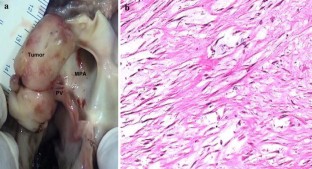

Fibroma, the second most common tumor in childhood, usually is a large solitary mass involving the ventricular septum or the left and rarely the right free ventricular wall. An unusual case of a 5.2-year-old boy with a large mass originating from the pulmonary valve is reported. The patient presented for evaluation of a murmur. Echocardiography and cardiac magnetic resonance imaging showed a large tumor extending from the distal right ventricular outflow tract through the pulmonary valve and into the main pulmonary artery causing moderate obstruction. The patient had a fatal cardiac arrest while awaiting surgery. The postmortem examination proved the tumor to be a fibroma.

Fig. 1